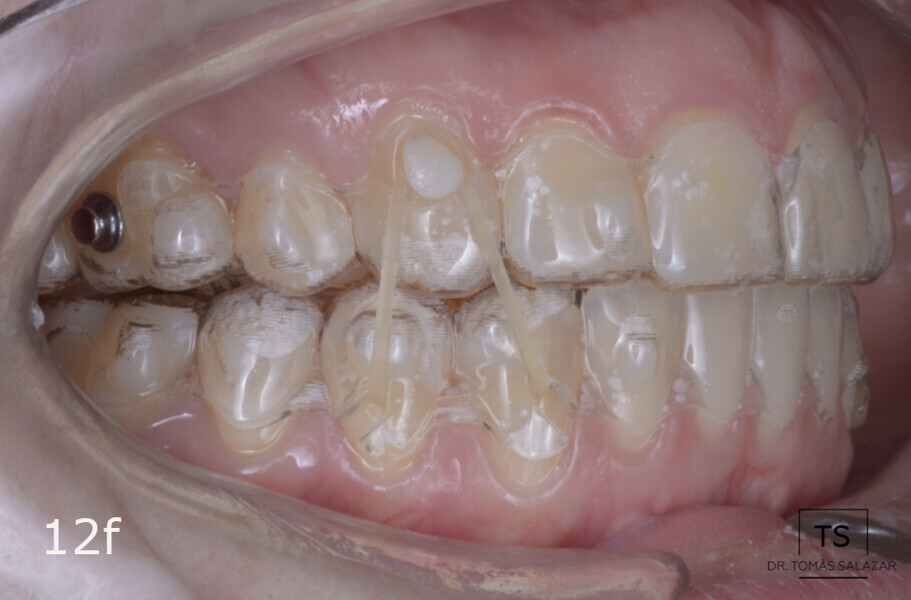

The treatment objectives included closing the anterior open bite, achieving a bilateral Angle Class I relationship and a proper overjet and overbite, correcting the midline discrepancies, and achieving a profile harmonisation. The treatment plan consisted of orthodontic camouflage treatment with asymmetric distalisation in three of the four quadrants using Invisalign aligners (Align Technology) and third molar extraction. The Invisalign Comprehensive package was chosen, and 63 pairs of aligners were used (Figs. 7–10). Each aligner was worn for 20 hours a day for one week each. The use of Class III elastics on both sides was indicated. Afterwards, ten refinement aligners were needed to improve the interdigitation on the right side (Figs. 11 & 12).